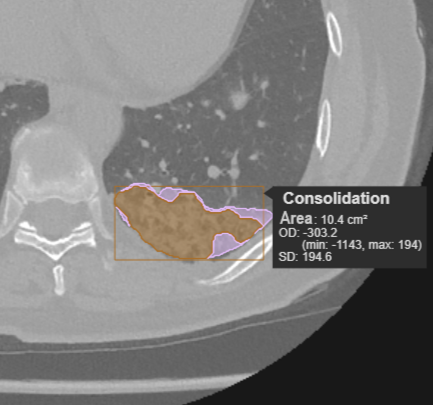

• Classifies nodules, masses, and pneumonia indicators for precise analysis

• Localizes pathologies with visual annotations on CT images